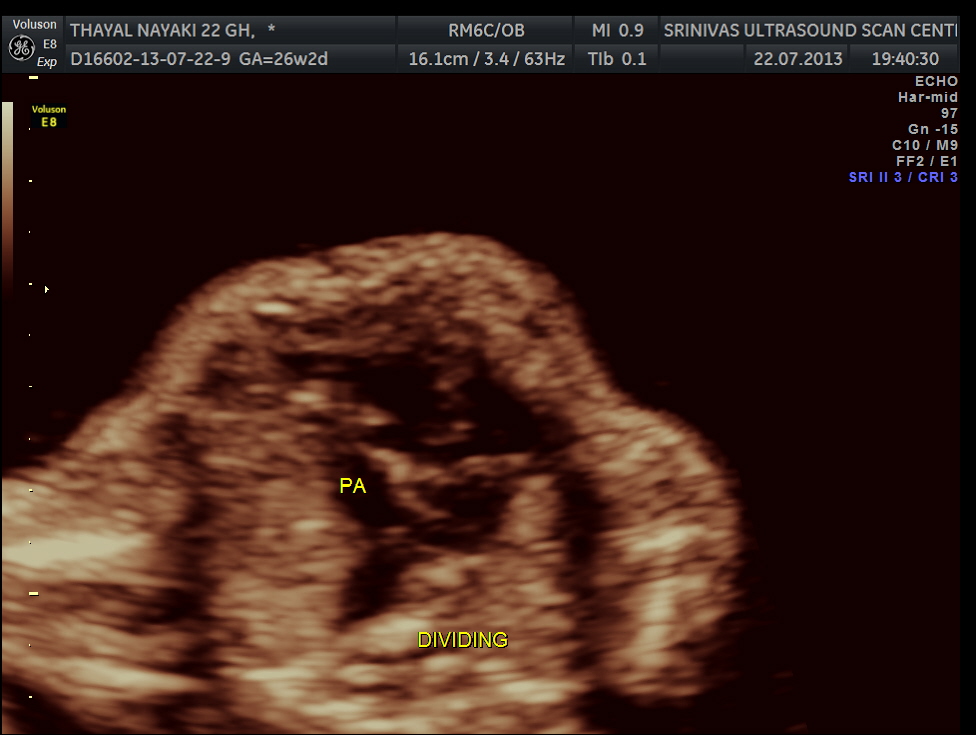

here we can see the pulmonary artery with its two branches arising from the lower (left) ventricle .and the aorta arising from the anterior (right ) ventricle.

pulmonary artery dividing into two

Under normal circumstances the chamber in front of descending aorta is left atrium ; and the aorta arises from the left ventricle which has no trabeculations ; the pumonary artery which divides into the two branches arises from the anterior right ventricle and crosses over the aorta .